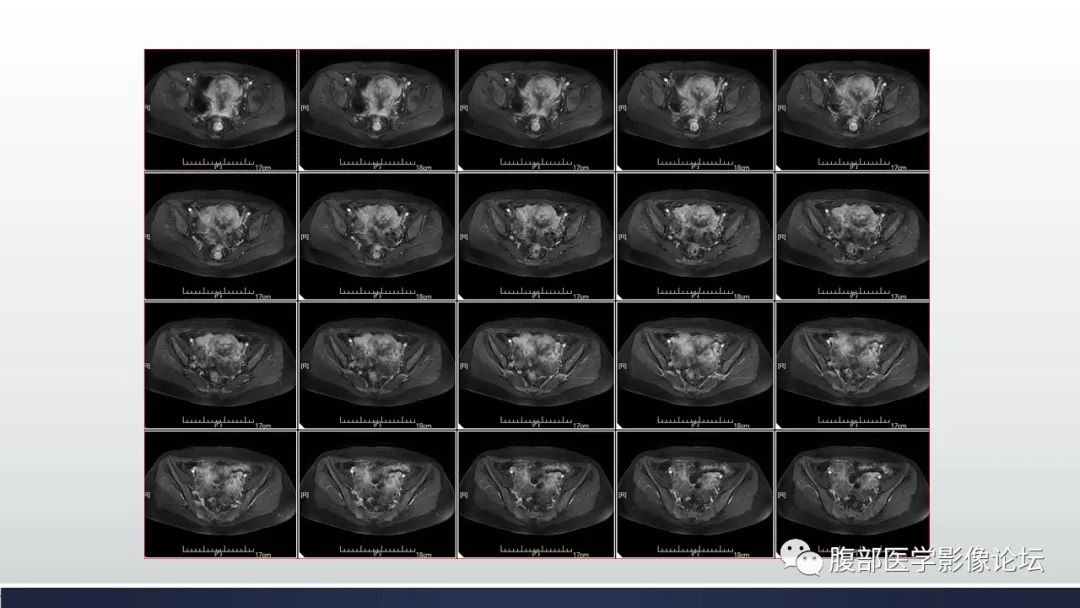

【病例】子宫内膜透明细胞癌1例MR-9

【病例】子宫内膜透明细胞癌1例MR-10

【病例】子宫内膜透明细胞癌1例MR-11

【病例】子宫内膜透明细胞癌1例MR-12